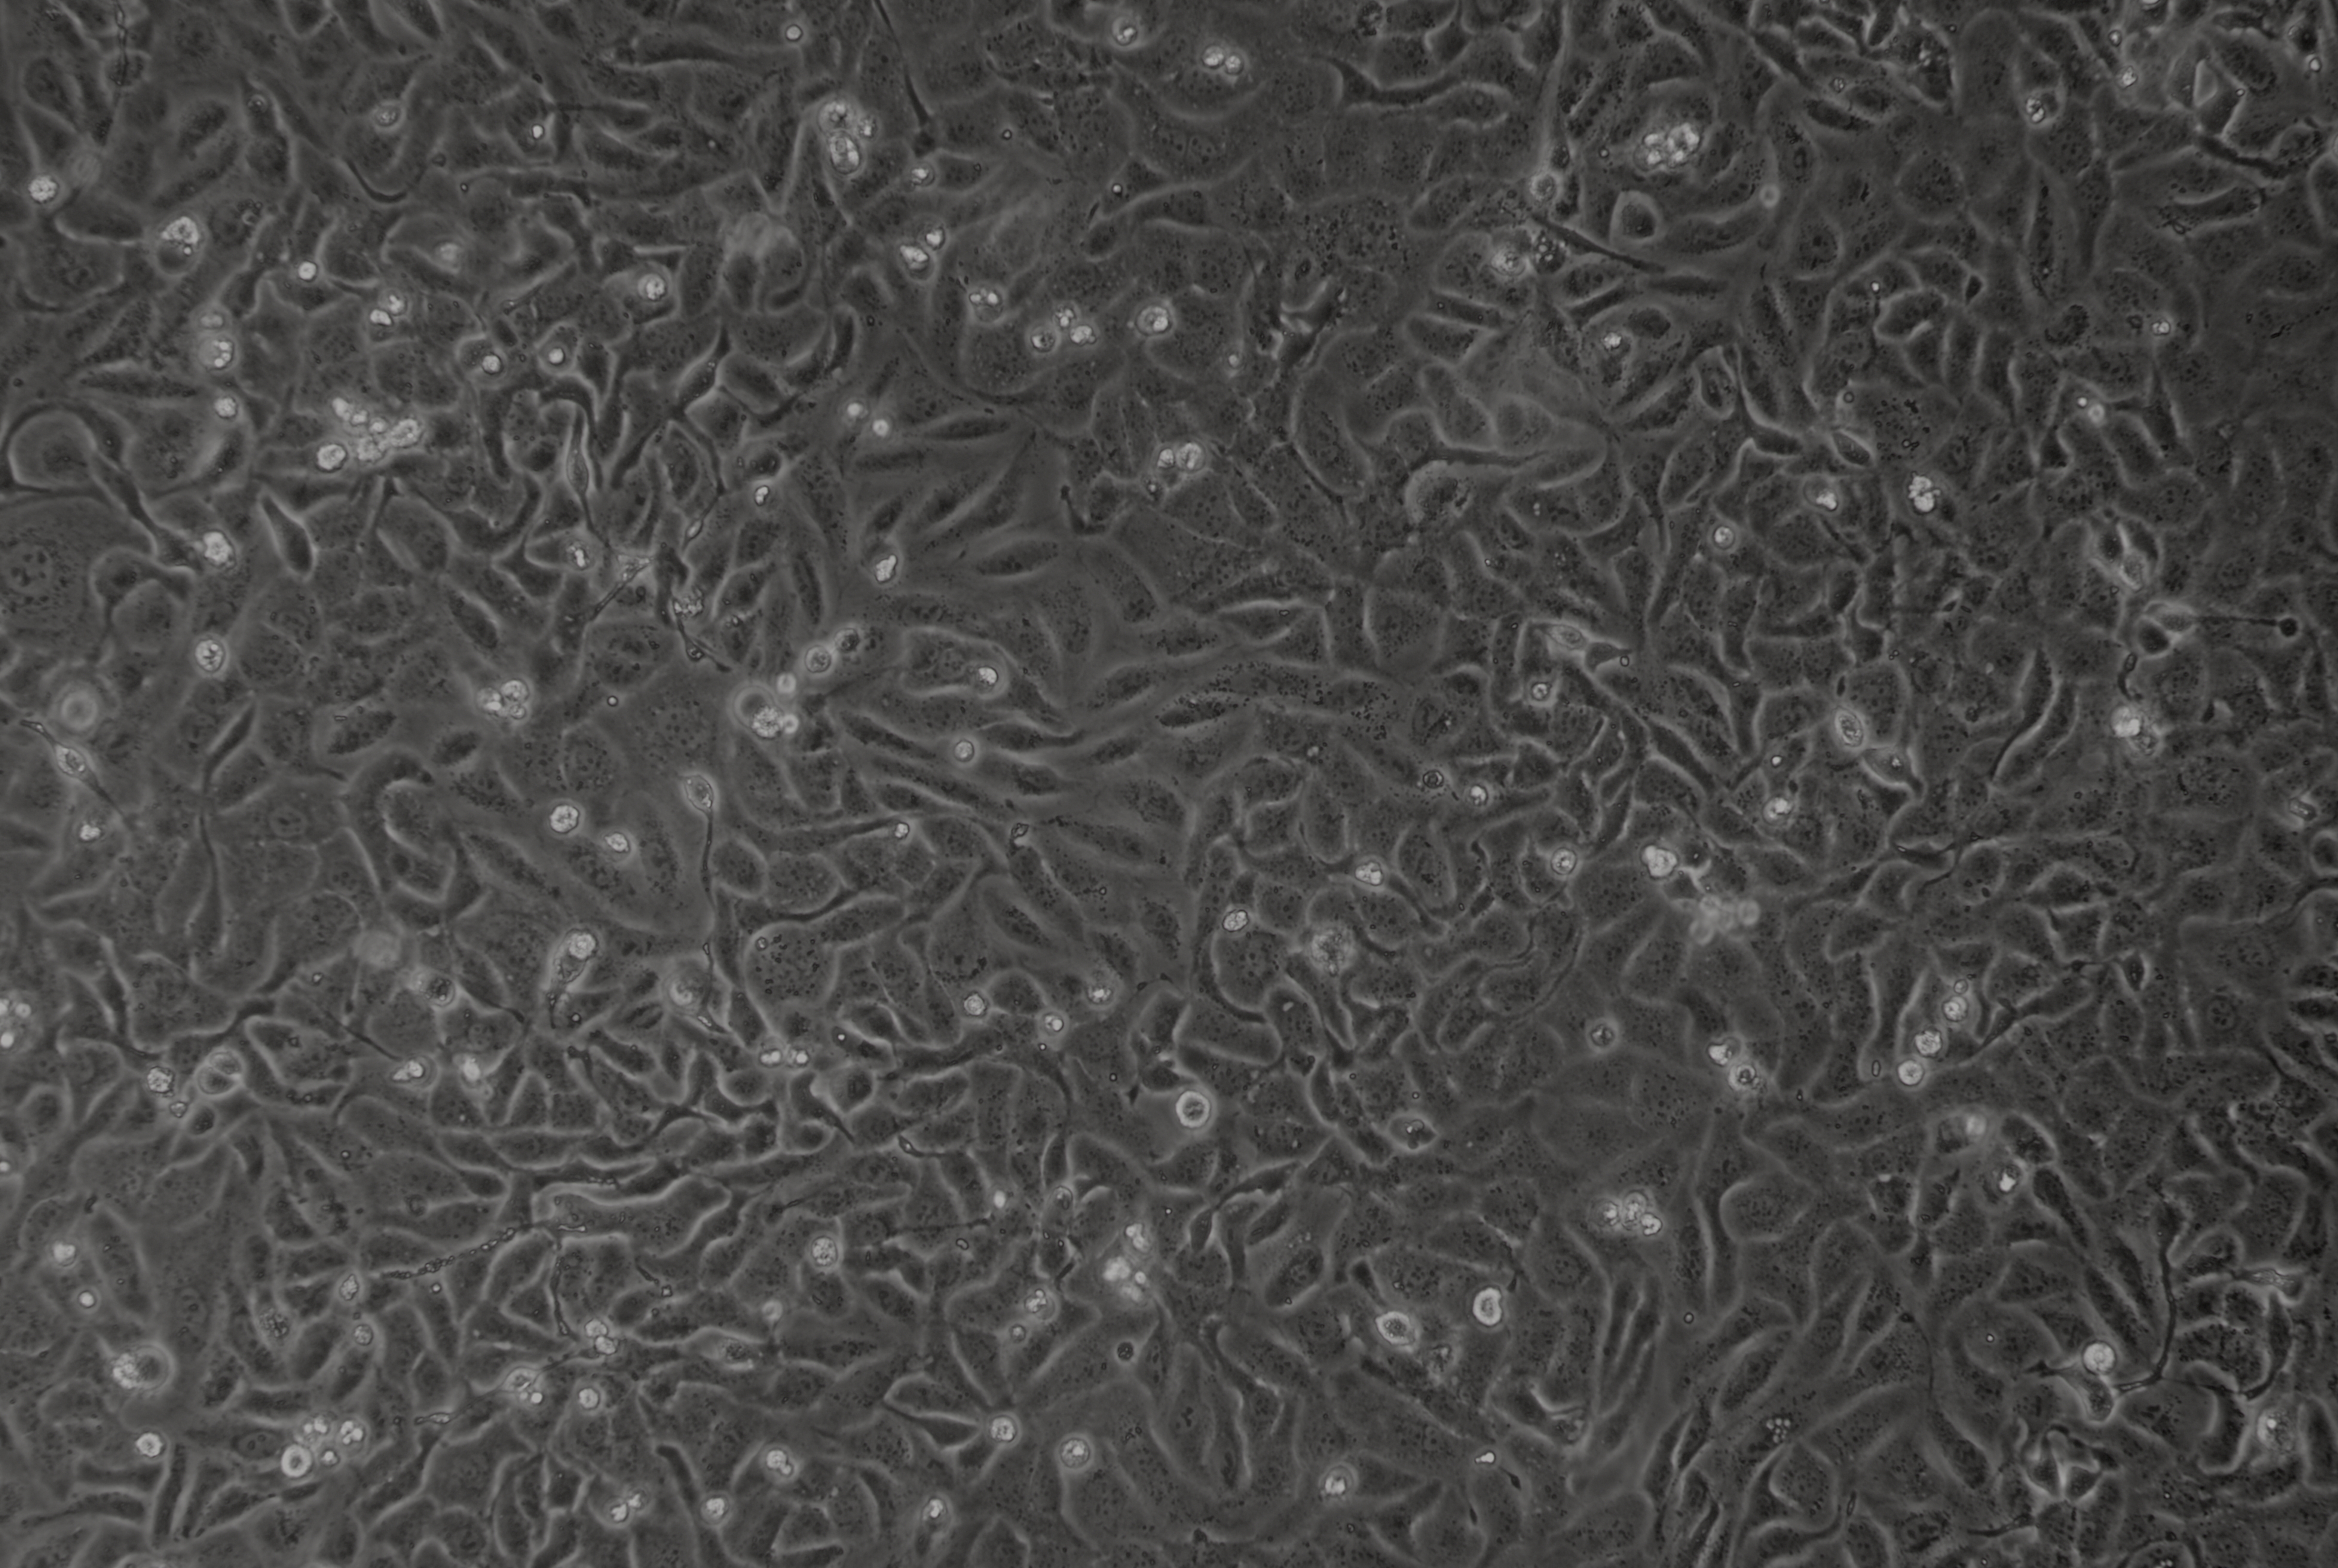

形態 |

上皮細胞 |

生長特征 |

貼壁生長 |